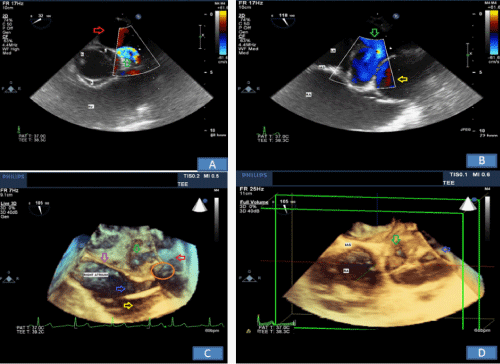

Intraoperative TEE ME SAX AV view with color Doppler shows a mosaic color pattern indicating blood flow in enlarged left main coronary artery and the fistula tract behind (Figure 3A). TEE ME Bicaval view with color Doppler indicates blood flow in distal left main coronary artery fistula and giant fistula aneurysm (Figure 3B) with different channeling tunnels seen per 3D (Figure 3C & Figure 3D), forming a complex network of trafficking communication between distal fistula tract, right atrium and giant aneurysmal CAF dilatation. The pulse wave Doppler through distal fistula tract allowed us to calculate velocity time integral (VTI) of 23.6cm (Figure 4). By equation: Volume=Area X VTI, the volume per heart beat shunted via fistula is calculated to be 47.2ml, using the measured cross sectional fistula diameter of 1.6cm (Area=2cm2), which equated to be 3.26L/min for the flow rate across the fistulous tract considering patient’s heart rate of 69beats/min. This shunting volume and flow rate indicated a significant L-R shunt, which correlated well with patient’s high CHF symptoms.

Figure 3a EE ME AV SAX View. A mosaic color flow pattern (located inside the triangular sample volume) indicates large left main coronary flow with fistula track formed (red arrow).

Figure 3bTEE ME Bicaval View with color Doppler prior to fistula ligation procedure. Green and yellow arrows indicate blood flow in distal left main coronary artery fistula and giant fistula aneurysm respectively.

LA: Left Atrium; RA: Right Atrium; IAS: Interatrial Septum

Figure 3cTEE Live 3D Zoom from Bicaval View. Purple arrow indicates interatrial septum. Green arrow indicates left main coronary artery fistula tract. Red arrow indicates giant fistula aneurysmal dilatation. Blue and yellow arrows indicate pathways between fistula and the right atrium. Orange oval indicate transit pathway into and out from the aneurysmal fistula.

Figure 3dTEE Full Volume 3D from Bicaval View. Green arrow indicates inflow from fistula track. Blue arrow indicates giant CAF aneurysm. There are different channeling tunnels seen, which form a complex network of trafficking communication between distal fistula track, right atrium and giant aneurysmal CAF dilatation. IAS: Interatrial septum; RA: Right atrium